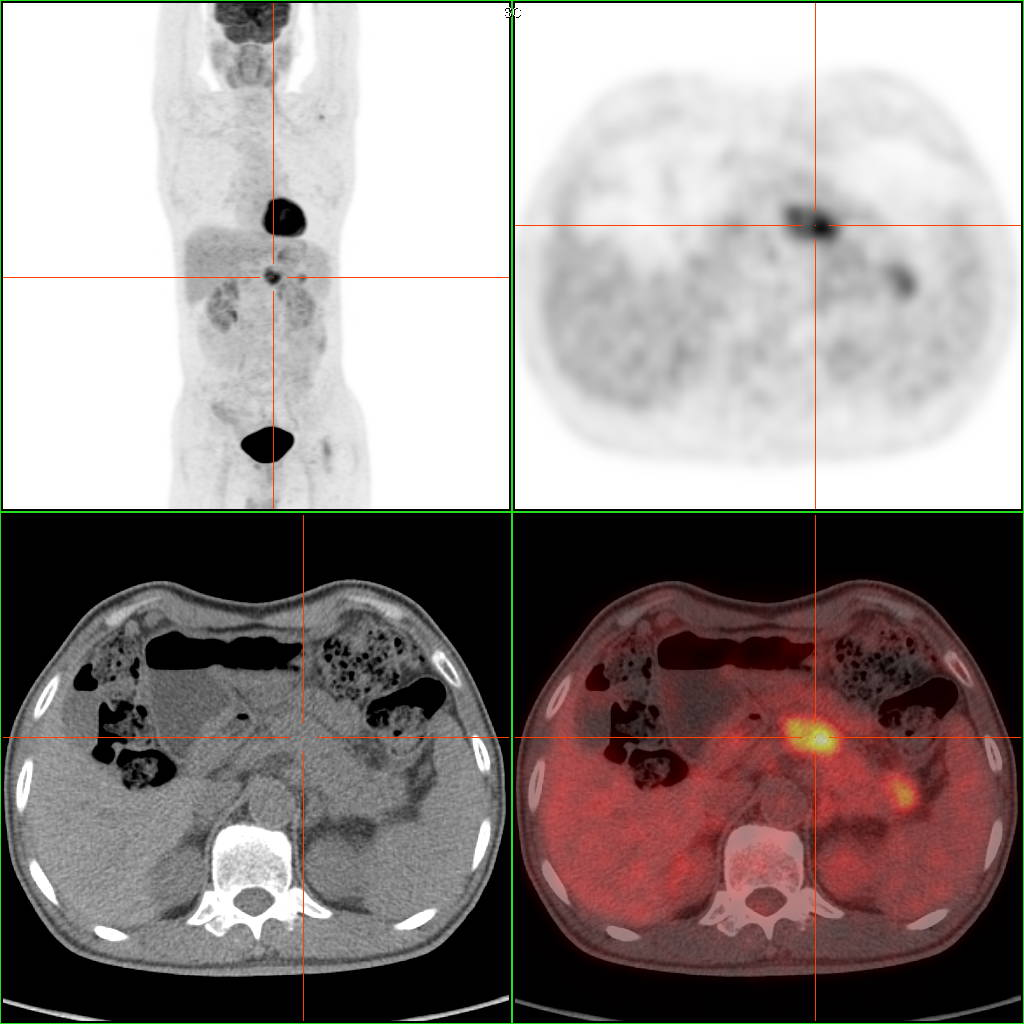

该病人无明显症状,CT检查发现胰腺头颈部稍丰满,无异常低密度改变,肿瘤标记物不高。PET/CT检 查明确诊断:胰腺头颈部早期胰腺癌。 PET/CT通过放射性示踪剂来检测组织的代谢活性,并结合CT的解剖信息,适合全身性的肿瘤检测和评估,显像剂到哪里,仪器就可以看到那个地方。

PET/CT检查因其在肿瘤筛查中的高效能力而被誉为“查癌神器”,它能够将功能性成像和解剖结构成像相结合,提供全面的诊断信息。是PET与CT合二为一的仪器,将两个图像叠加在一起。

PET/CT不仅能够识别身体中的异常组织是否为肿瘤,还能评估肿瘤的阶段、定位肿瘤细胞在体内的分布、勾画放疗靶区、精准定位穿刺活检位置,并监测肿瘤治疗的效果。通过在治疗前后各进行一次PET/CT扫描,并将两次的影像资料进行对比分析,医生可以直观地观察到治疗效果,从而为制定或调整治疗计划提供重要依据。